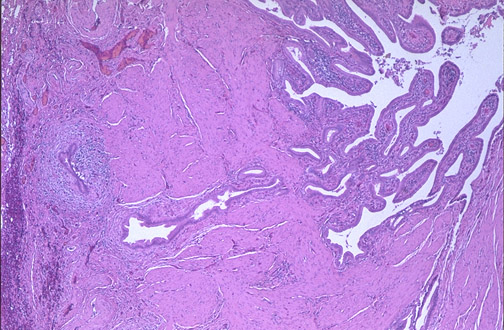

| Chronic cholecystitis almost always occurs in association with gallstones, though precipitation of bile alone may be sufficient to produce inflammation. There may not be a history of bouts of acute cholecystitis. Seen here is a thickened gallbladder wall along with outpouchings of mucosa (Rokitansky-Aschoff sinuses). |